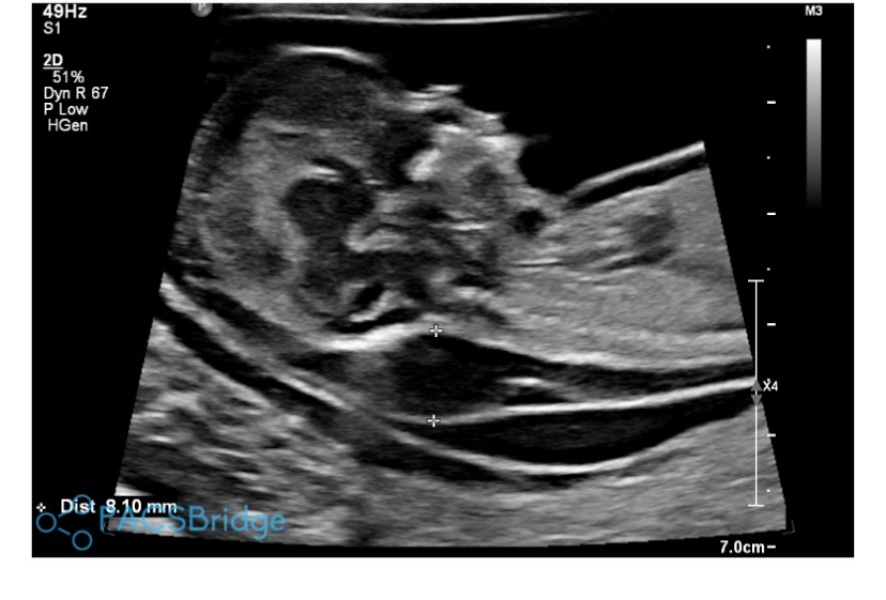

8.1 NT, no physical abnormalities, lots of excess fluid at 13 weeks

8.1 NT result as well as fluid around a lot of baby including around the heart and lungs.

On a positive note, the doctor has said there doesn't appear to be any physical abnormalities so she's tentatively ruled out T18 and T21 but cannot be 100% until the CVS results are back.

Baby is also super active on scans, not lethargic at all.

I'm really sorry this has happened to you. We had a very active baby on the scan and a NT of 8-8.5mm. We left the scan feeling that whatever was wrong, it was unlikely to have a good outcome. I researched and convinced myself it was Turners due to the high NT, but it turned out to be T18 - we had a NIPT as there was a two week wait for an appt for a CVS. The NIPT came back high risk for T18 and the post mortem following a TFMR confirmed it.